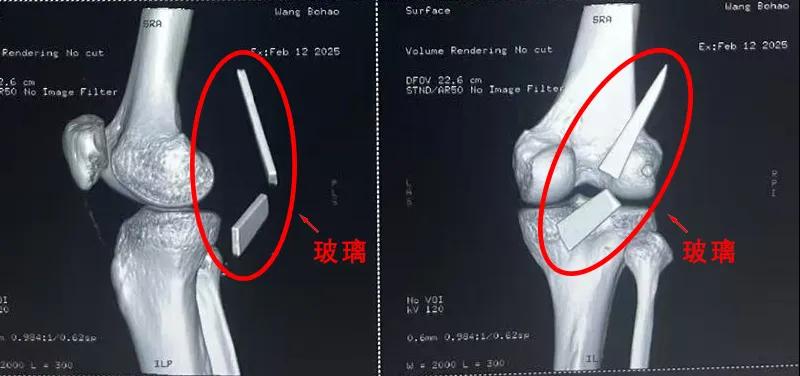

13厘米碎玻璃扎入腿中,漯河醫(yī)專二附院顯微外科緊急“拆彈”......

“兩塊碎玻璃加起來有13cm長,這要是傷到了血管,后果可是不敢設(shè)想......”雖然手術(shù)已經(jīng)順利結(jié)束,回憶起當時的畫面,患者家屬還是心有余悸。

患者家屬這才開始意識到問題的嚴重性,便帶著孩子到鄉(xiāng)鎮(zhèn)衛(wèi)生院檢查——結(jié)果顯示右膝關(guān)節(jié)后方竟然殘留著兩塊兒鋒利的碎玻璃,測量后預估玻璃總長將近13厘米!

由于玻璃位置毗鄰坐骨神經(jīng)和股動脈,一旦刺破股動脈,將嚴重威脅生命。家屬著急萬分,想著能否盡快手術(shù)取出碎片,于是慕名來到漯河醫(yī)專二附院(漯河市骨科醫(yī)院、漯河市立醫(yī)院)手顯微外科(修復重建骨感染科)。

術(shù)中,馬廣輝醫(yī)生憑借扎實的理論知識和嫻熟的顯微外科技術(shù),順利找到深深刺進肌肉的兩塊玻璃,肉眼可見玻璃尖端距股動脈僅有不到半公分的距離!如果患者再耽誤半天或者再多活動幾次膝關(guān)節(jié),小指粗的股動脈很有可能被玻璃扎破,后果難以想象。

最終,馬廣輝醫(yī)生在血管、神經(jīng)表面順利取出兩塊玻璃碎片,拆除了埋在患者膝關(guān)節(jié)的“炸彈”。在告知患者家屬術(shù)中情況后,家屬懸著的心終于放了下來。